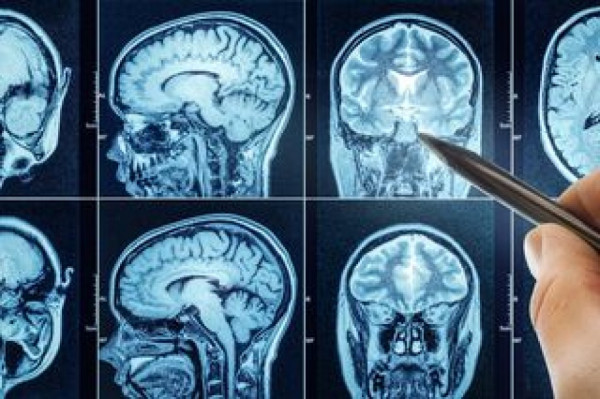

В центре внимания — инновационная методика, сочетающая лазерную интерстициальную термотерапию (LITT) и иммунотерапию. Суть процедуры заключается в том, что нейрохирурги под контролем МРТ вводят в опухоль тончайший зонд и с помощью лазера нагревают пораженные ткани. Это позволяет разрушить раковые клетки, не затрагивая здоровые участки мозга. Но главное — временно нарушается так называемый гематоэнцефалический барьер, который обычно защищает мозг от проникновения вредных веществ, но одновременно мешает лекарствам и иммунным клеткам добраться до опухоли.